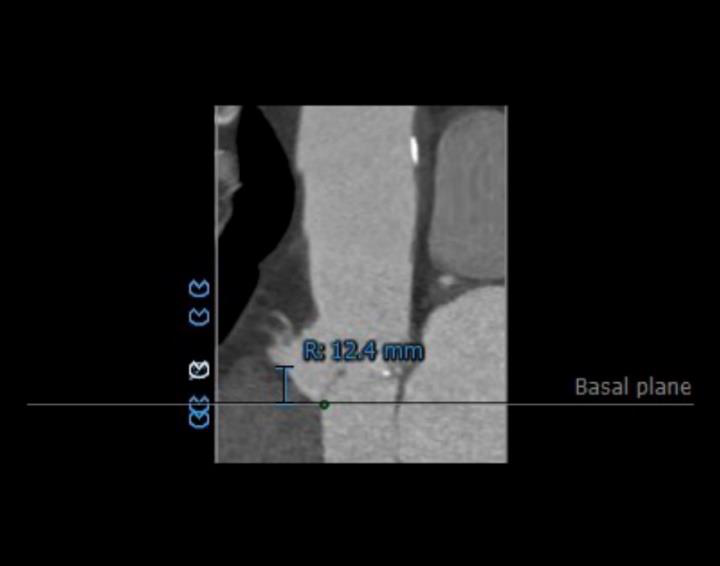

左右冠开口高度可,右冠多发钙化,依据瓦氏窦宽度和瓣叶长度预估右冠风险较小,左冠存在堵塞风险。

瓦氏窦内径、窦管交界内径偏小。升主内径尚可,主动脉瓣环与水平面夹角可,主动脉弓角度与宽度可。

①瓦氏窦整体形态偏小,钙化程度较轻。

主动脉根部评估:

瓣环上解剖及钙化分布:

主动脉根部造影提示瓦氏窦整体形态偏小,决定给予冠脉保护